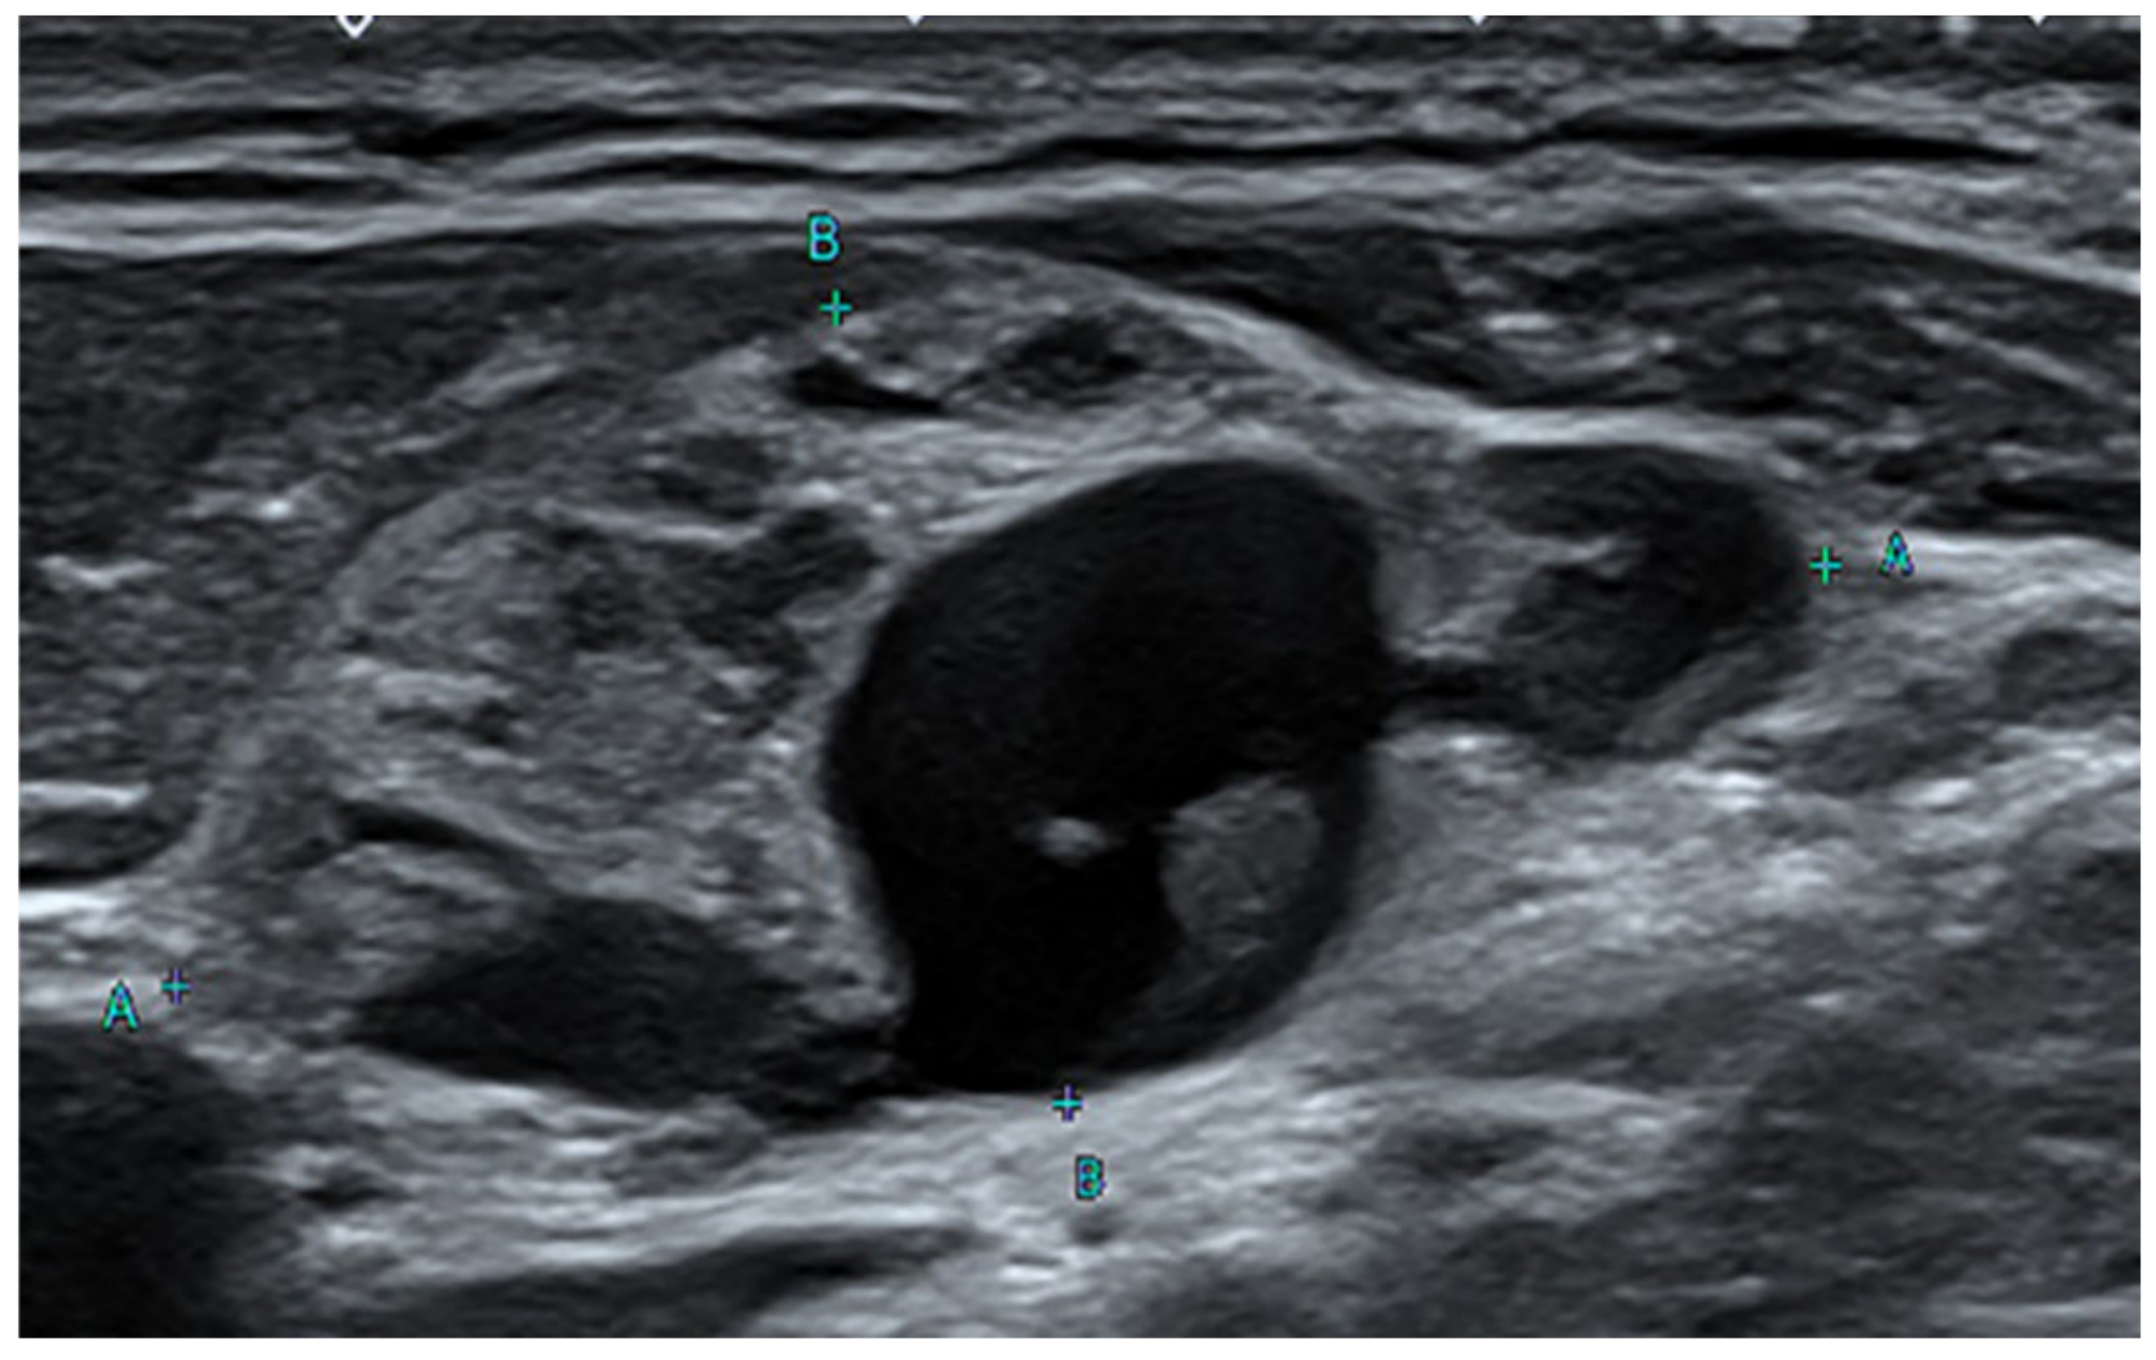

Figure 1.

Ultrasound sonography (US) of the neck. Neck US reveals an enlarged lymph node with internal cystic change at left level III. A few cases of non-malignant inclusions were detected in lymph nodes removed from a patient with malignancies. For example, benign salivary glands in the pulmonary hilar lymph node, benign epithelial tissue, nevus cells in the axillary node, and benign Mullerian inclusions in the pelvic and paraaortic lymph nodes have been found [1,2,3,4,5]. There have been many reports since the first report of an intranodal inclusion of benign thyroid tissue in 1897, but the origin and mechanism of intranodal thyroid tissue are not clear [6,7,8,9,10]. Furthermore, there have been few radiographic pathological reports of very extensive cystic changes in benign thyroid tissue in the lymph nodes. A 47-year-old male patient visited the hospital 3 years ago complaining of discomfort in the left side of the neck. Ultrasound sonography (US) revealed thyroid nodules of various sizes with bilateral cystic changes. The thyroid function test was normal with T3 0.66 ng/mL, Free T4 1.36 ng/dL, and TSH 1.48 uIU/mL. Fine needle aspiration was performed to confirm nodular hyperplasia of the thyroid gland. Three months later, the size of the thyroid gland had increased. Therefore, direct injection of ethanol through the needle for the atrophy of a thyroid mass, the so-called ethanol sclerotherapy [11], was performed. The following day, he had trouble breathing with fever, chills, and myalgia. Computed tomography (CT) of the neck revealed a purulent cystic mass with conglomerated lymph nodes in the left neck. WBC 14,530/µL, ESR 120 mm/h, and CRP 39 mg/L were observed in the blood tests. A purulent abscess was clinically suspected and subtotal left lobectomy was performed along with abscess removal. An abscess of the neck and nodular hyperplasia of the thyroid gland were confirmed histologically. Four months later, a mediastinal mass was detected, and an invasive thymoma was diagnosed via total thymectomy. US of the neck performed 2 months prior showed enlarged lymph nodes at left neck levels II and III, and increased blood flow in the solid part (Figure 1). Polymerase chain reaction (PCR) test for Mycobacterium tuberculosis was negative, and the BRAF V600E mutation was not detected. CT of the neck revealed multiple nodular lymph node masses from left neck levels II, III, and IV to the superior mediastinum (Figure 2).